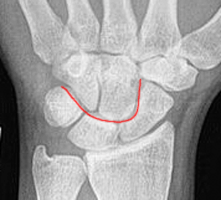

• Kontinuität der drei Karpalbögen:

Proximaler Bogen: proximale Gelenkflächenkonturen von Scaphoid, Lunatum und Triquetum

Mittlerer Bogen: distale Gelenkflächenkonturen von Sacphoid, Lunatum und Triquetum

Distaler Bogen: proximale Gelenkflächenkonturen von Capitatum und Hamatum

Fehlende Abgrenzbarkeit, Versatz oder Unterbrechung sind als pathologisch zu bewerten und deuten auf eine Luxation hin.

Cave: SL-Dissoziation (Ruptur des SL- Bandes, häufigste Gefügestörung): Terry-Thomas-Sign = SL-Spalt > 3mm, Siegelringzeichen = Ringförmige Transparenzminderung im mittleren Scaphoiddrittel durch orthograde Projektion der Taille infolge Rotation.